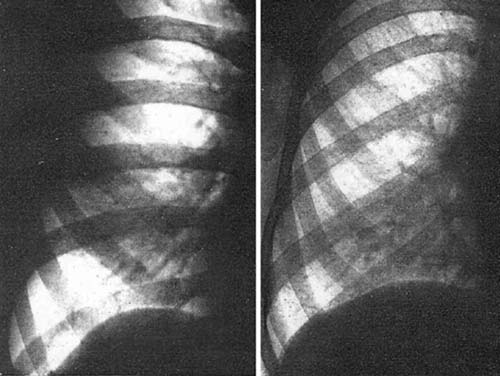

図11. 左図.肺梗塞.右下肺野の陰影内に,明るい線条陰影(気管支の透亮像)が認められる.右図.葉間胸水.右下肺野の陰影内には暗い線条陰影(血管陰影)が認められる.

【要旨・解説】肺実質性病変を示唆する基本的なレントゲンサインとして知られるair bronchograms の初報である.著者は,肺野の均一な陰影内の明るい線条構造に気づき,その樹状構造から気管支と考えた(図11).このよう濃厚陰影内の気管支透亮像は,肺炎,肺梗塞など肺実質病変で認められ,胸膜病変(胸水)では認められない.胸膜病変,特に葉間胸水の貯溜でみられる陰影は肺病変との鑑別を要することがあるが,この所見があれば鑑別しうると結論している.

しかし著者が "Der sichtbare Bronchialbaum"と呼ぶこの所見は,その後いくつかの教科書に引用されたもののあまり一般に知られることはなかったようで,このおよそ20年後,1948年にあらためてほぼ同じ内容を,今度は英語で "The visible bronchial tree" として報告している[24].現在広く使われている "air bronchograms" の初出は,後にFelsonがその名著 Chest Roentgenology [21] でこの文献を引用して使用したものである.